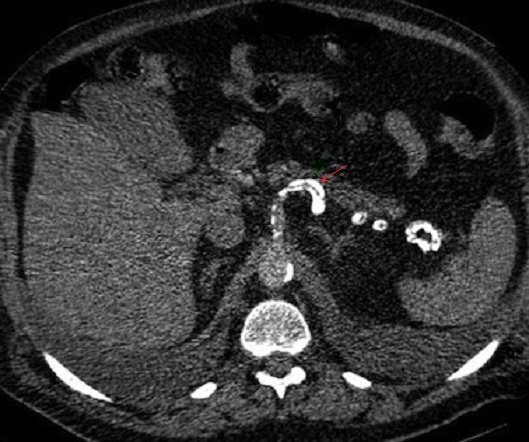

On doit en distinguer avec

image de calcification vasculaire en rail de train

tres hyperdense de artere splenique ( fleche rouge )

. Image radiologique TDM d'une pancreatite chronique

avec image de calcification de artere splenique en

coupe axiale |